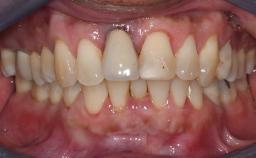

Missing Maxillary Central Incisor, Single Implant Replacement with Adjacent Tooth Restoration

The patient presented with a failing tooth-supported fixed dental prosthesis with cantilever extension replacing the right maxillary central incisor. His chief presenting complaint was poor esthetics, in particular the dark discolored margin around the abutment tooth, the maxillary left central incisor. He reported a history of trauma at a young age, which necessitated the replacement of his maxillary right central incisor as well as root canal therapy of the adjacent left central incisor. The existing prosthesis had been in situ for over 20 years. The initial periapical radiograph displayed good proximal bone levels at the adjacent teeth and a wide incisive canal, which was a concern. The left central incisor presented a very wide root canal treatment with compromised radicular dentin thickness, which was a consideration in the decision between a new tooth-supported fixed dental prosthesis vs. an implant-supported prosthesis. After a lengthy discussion on the risks and benefits of both treatment options, the patient decided on a single-tooth implant replacement.

Esthetic Risk High

Provisional Implant-Supported Prosthesis Prosthodontic margin > 3 mm apical to mucosal margin Prosthodontic margin > 3 mm apical to mucosal margin